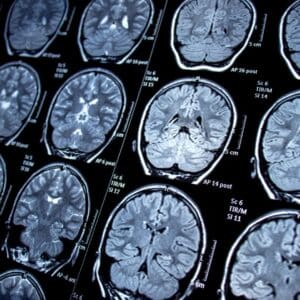

High-Resolution Magnetic Resonance Imaging (MRI)

At Atlanta Neuroscience Institute, we utilize state-of-the-art high-resolution MRI technology to capture detailed brain structure images. This advancement allows our neurologists to identify subtle abnormalities and provide precise diagnoses. The high level of detail offered by this technique enhances our ability to detect conditions such as tumors, vascular malformations, and other structural anomalies with unparalleled accuracy.